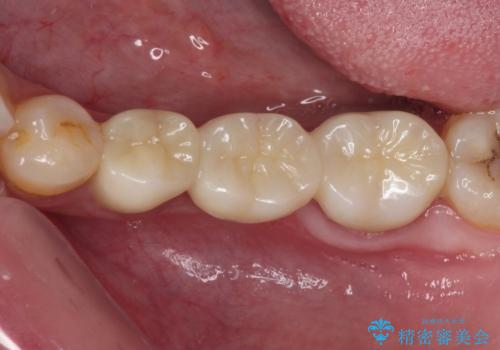

むし歯だらけの奥歯 セラミッククラウンによるむし歯治療

根管治療や歯周外科処置後にフルジルコニアクラウンにて補綴治療することとしました。

再発や他の歯がむし歯となるリスクを低減させるため、日頃からのプラークコントロールと定期的なクリーニングが重要となります。